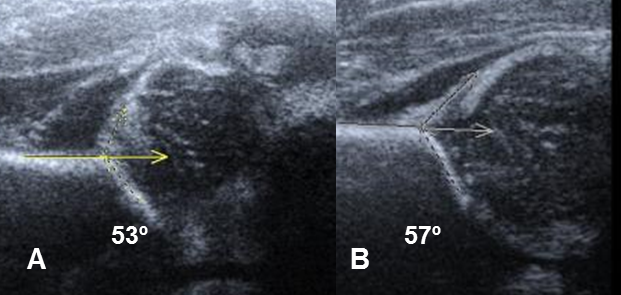

El ángulo alfa es importante para la valoración de la displasia de cadera. Un ángulo mayor de 60º es normal para cualquier edad. Entre 50º y 59º, puede ser normal para niños menores de 3 meses, pero se recomienda el seguimiento y un ángulo menor de 50º, es anormal en cualquier edad. (2). (Fig 33 A).

La displasia se puede clasificar en severa: ángulo menor de 43º, moderada: entre 43º y 49º y leve: entre 50º y 59º. (6). (Fig 33 B).

Fig 33 A. Cadera inmadura.

A y B: Ecografías. Angulos alfa entre 50 y 60º, por caderas inmaduras y se recomienda el seguimiento.